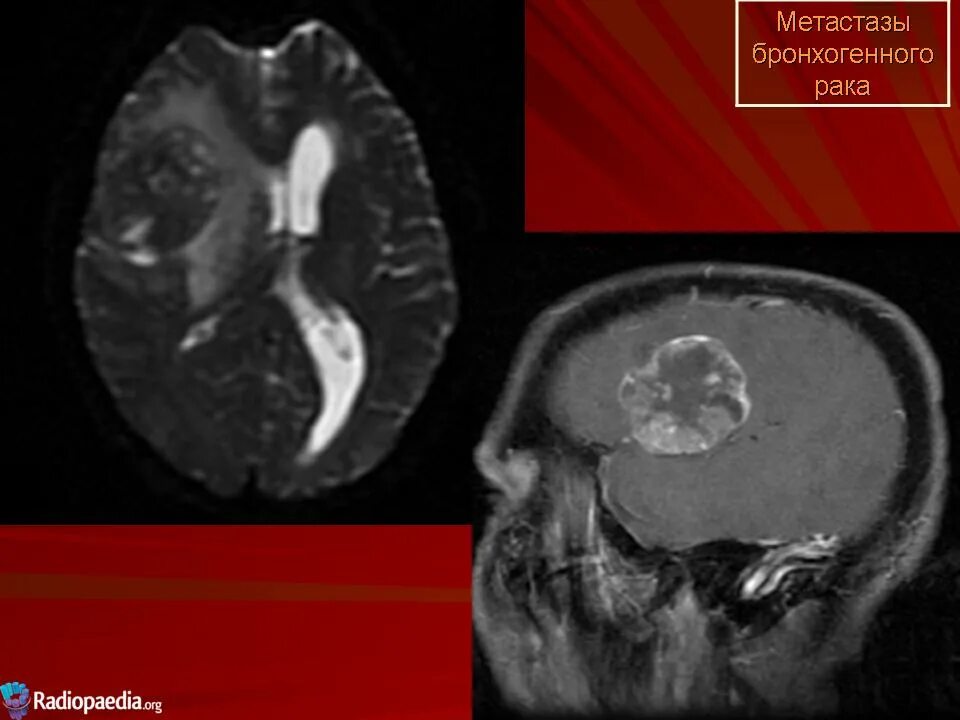

Метастазы в головном мозге мкб